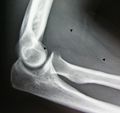

- Resection of an intermuscular lipoma in the elbow region

The operating field after removal of the lipoma. Arrow marks the median nerve which was compressed by the lipoma.